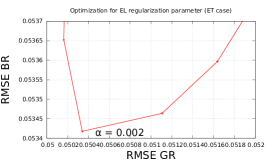

For a fair comparison of different regularizing penalties we initially optimized the regularization parameters (see Fig. 2) with respect to the value of root-mean-square-error (RMSE), defined as:

We found empirically that for EL penalty (20) gives good results for the presented experiments, therefore we will keep it fixed for the rest of our tests. With fixed optimal regularization parameters (see Fig. 2) we perform outer (fixed point) iterations and 5 inner iterations of algorithm 1 with different penalties (see Fig. 3).

To quantify obtained reconstructions we used averaged over all noise realizations RMSE (23) values in the bone region (BR) and in Gaussian regions (GR). All regularization parameters were carefully selected by comparing the mean of all RMSE values over all noise realizations in GR and BR (see Fig. 8).